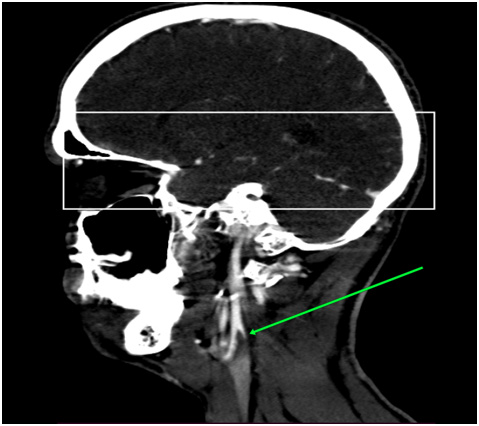

Via native and contrast CT scan intracranial hemorrhage was excluded and the contrast CT scan revealed a thrombus in the left internal carotid artery (Figure 1&2). Doppler ultrasound was also performed which showed a carotid stenosis, caused by a mural thrombus (Figure 3). Treatment with tissue plasminogen activator Actilyse was initiated. The total dose was 63 mg, 6 mg of which administered as a bolus i.v. injection and the remaining 57 mg were given as a continuous infusion for one hour. In the next 24 hours the patient received a heparin infusion, according to the aPTT values.